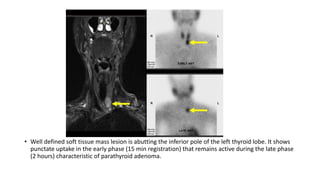

• Well defined soft tissue mass lesion is abutting the inferior pole of the left thyroid lobe. It shows

punctate uptake in the early phase (15 min registration) that remains active during the late phase

(2 hours) characteristic of parathyroid adenoma.